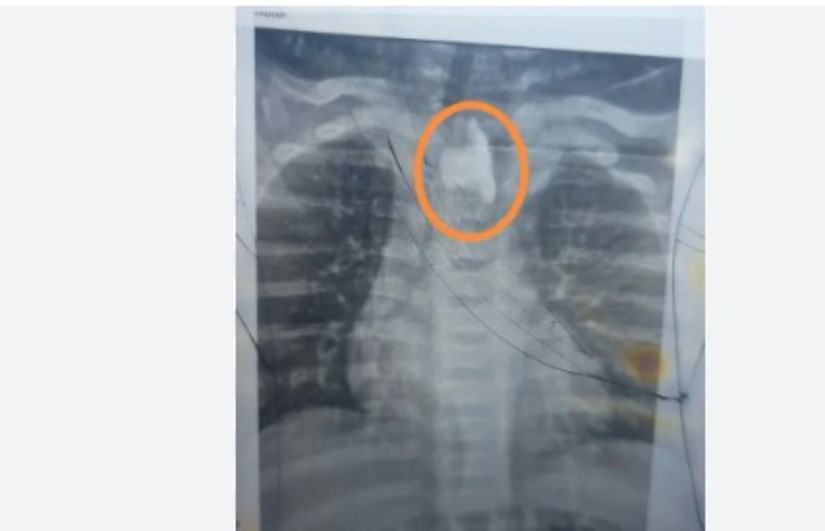

نجح فريق وحدة مناظير الجهاز الهضمي للأطفال بمستشفى بني سويف الجامعي في استخراج جسم غريب "زلطة" من مريء طفل يبلغ من العمر 10 شهور، بعد اكتشافه بالصدفة أثناء إجراء فحوصات طبية للاطمئنان على حالته الصحية.

وكان الطفل دخل قسم الأطفال وهو يعاني من التهاب حاد بالشُعب الهوائية وصعوبة في التنفس، وبعد عدم استجابته للعلاج المنزلي، تم حجزه بالمستشفى وخلال الفحوصات، تم طلب أشعة عادية على الصدر، والتي كشفت عن وجود جسم غريب في الجزء العلوي من المريء، تسبب في انسداد مجرى الطعام.

وعلى الفور، جرى تجهيز الطفل طبيًا، وخضع لمنظار معدة عاجل، أسفر عن استخراج "زلطة" كانت مستقرة بالمريء منذ فترة، ومتغلغلة في الأغشية، دون علم أسرته.